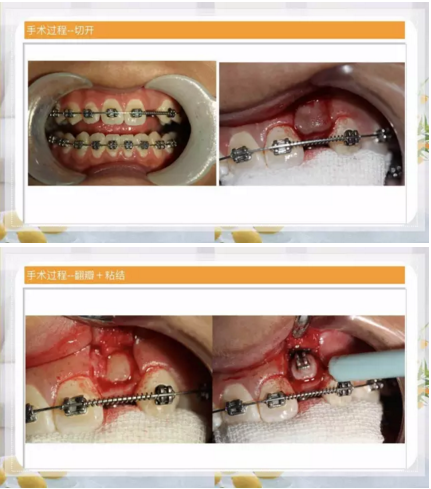

阻生齒外科聯(lián)合正畸治療

24.png

25.png

26.png

27.png

28.png